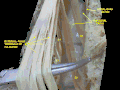

![]() Cauda equina and filum terminale seen from behind. The dura mater has been opened and spread out, and the arachnoid has been removed. (Filum terminale (internum) labeled at center right.) | |

The proximal/superior part – the filum terminale internum or pial part of terminal filum[3] – measures 15 cm in length and extends as far as the inferior border[1] of the second sacral vertebra (S2)[1][2] (the inferior limit sacral canal[2]). It is composed of the vestiges of neural tissue, connective tissue, and neuroglial tissue lined by pia mater.[3] It is contained within a tubular sheath of the dura mater and is surrounded by the nerves of the cauda equina (from which it can be easily recognized by its blueish-white color).[1]

The filum terminale is situated centrally[2] amid the spinal nerve roots of the cauda equina[3][2] (but is not itself a part of the cauda equina[2]).